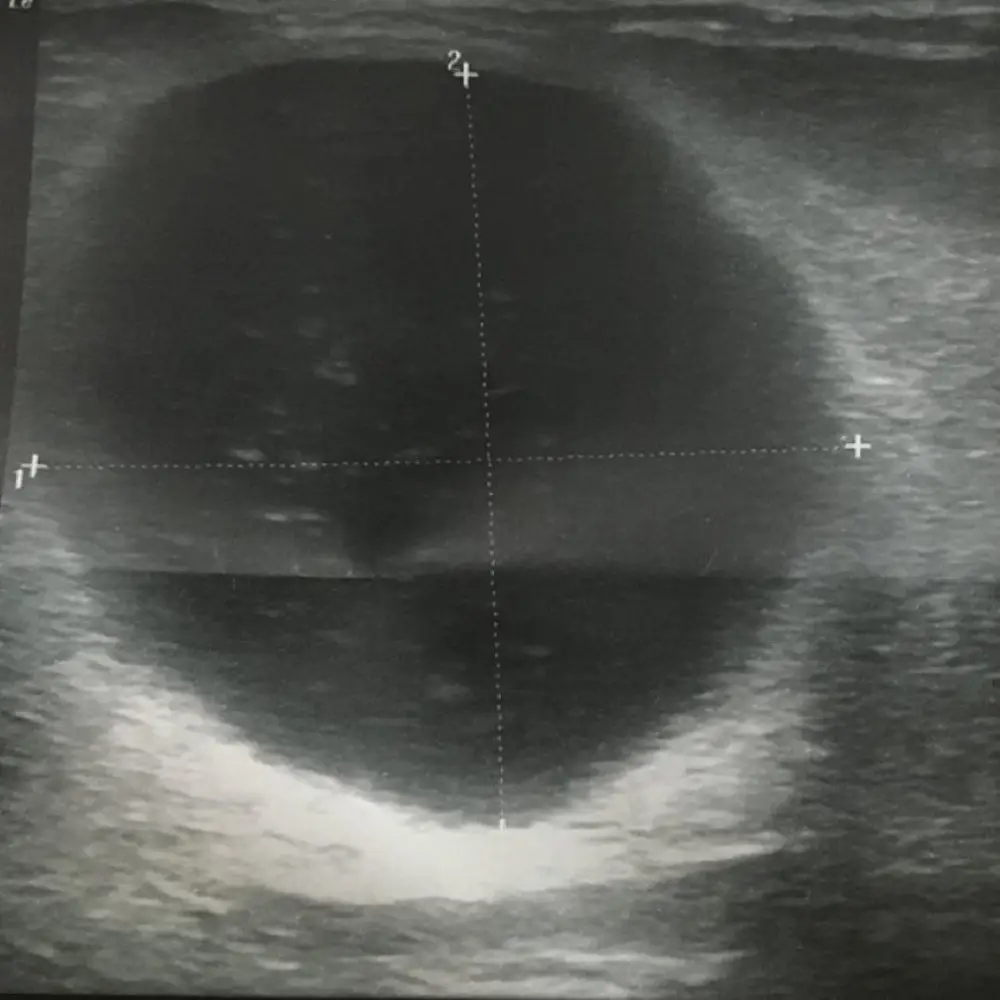

Breast cysts